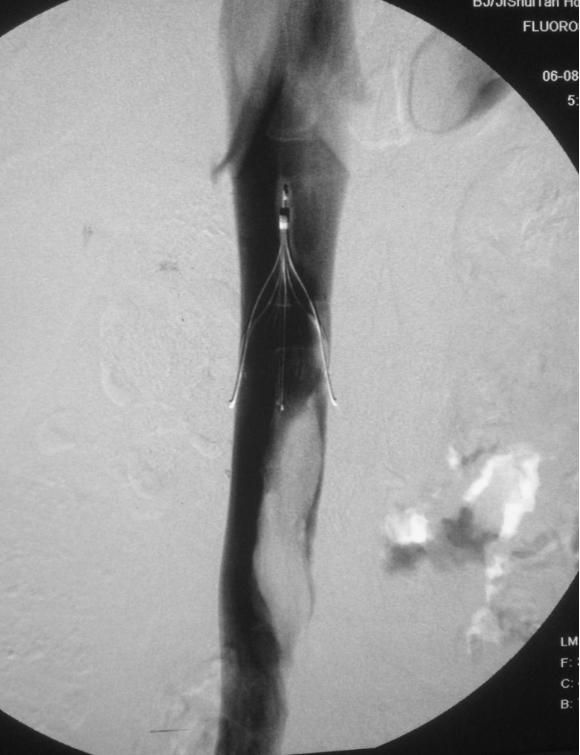

植入的下腔静脉滤器拦阻了大血栓,预防致死性肺栓塞